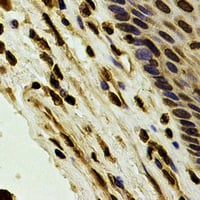

IHC (Immunohiostchemistry)

(Immunohistochemical analysis of Karyopherin alpha-4 staining in human esophageal cancer formalin fixed paraffin embedded tissue section. The section was pre-treated using heat mediated antigen retrieval with sodium citrate buffer (pH 6.0). The section was then incubated with the antibody at room temperature and detected using an HRP conjugated compact polymer system. DAB was used as the chromogen. The section was then counterstained with haematoxylin and mounted with DPX.)